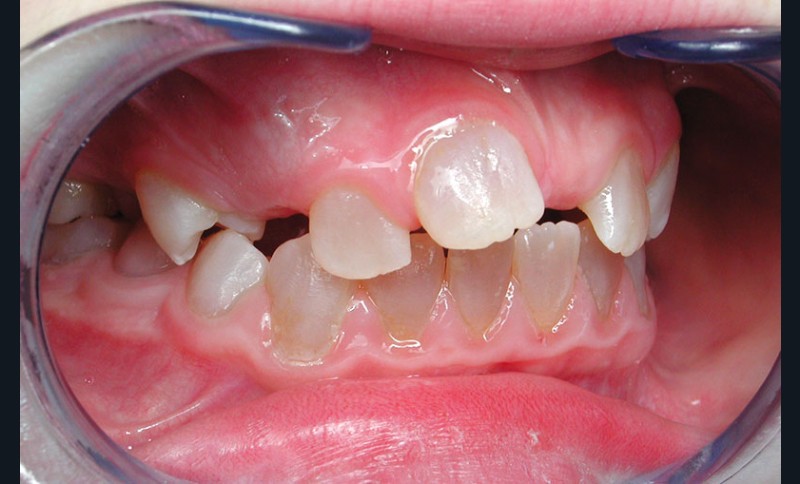

Teinte opalescente grise à jaune ambrée, couronnes globuleuses, calcifications intra-pulpaires, racines fines et courtes, attrition précoce, nécrose aseptique… Ces anomalies cliniques et radiographiques décrivent le tableau de la dentinogenèse imparfaite (DI) isolée de type 2. Cette anomalie génétique à transmission autosomique dominante est liée à un défaut de DSPP, gène de la sialophosphoprotéine dentinaire [1, 2]. Des anomalies dentinaires similaires résultent également de mutations de ce gène. Les avancées en recherche génétique tendent à réunir ces pathologies sous une même étiologie.

Un diagnostic précoce est primordial, car il existe aussi une forme associée à une anomalie osseuse, l’ostéogenèse imparfaite. Le chirurgien-dentiste est donc au premier plan pour dépister ces anomalies et limiter dès le plus jeune âge leurs conséquences infectieuses, fonctionnelles et esthétiques.